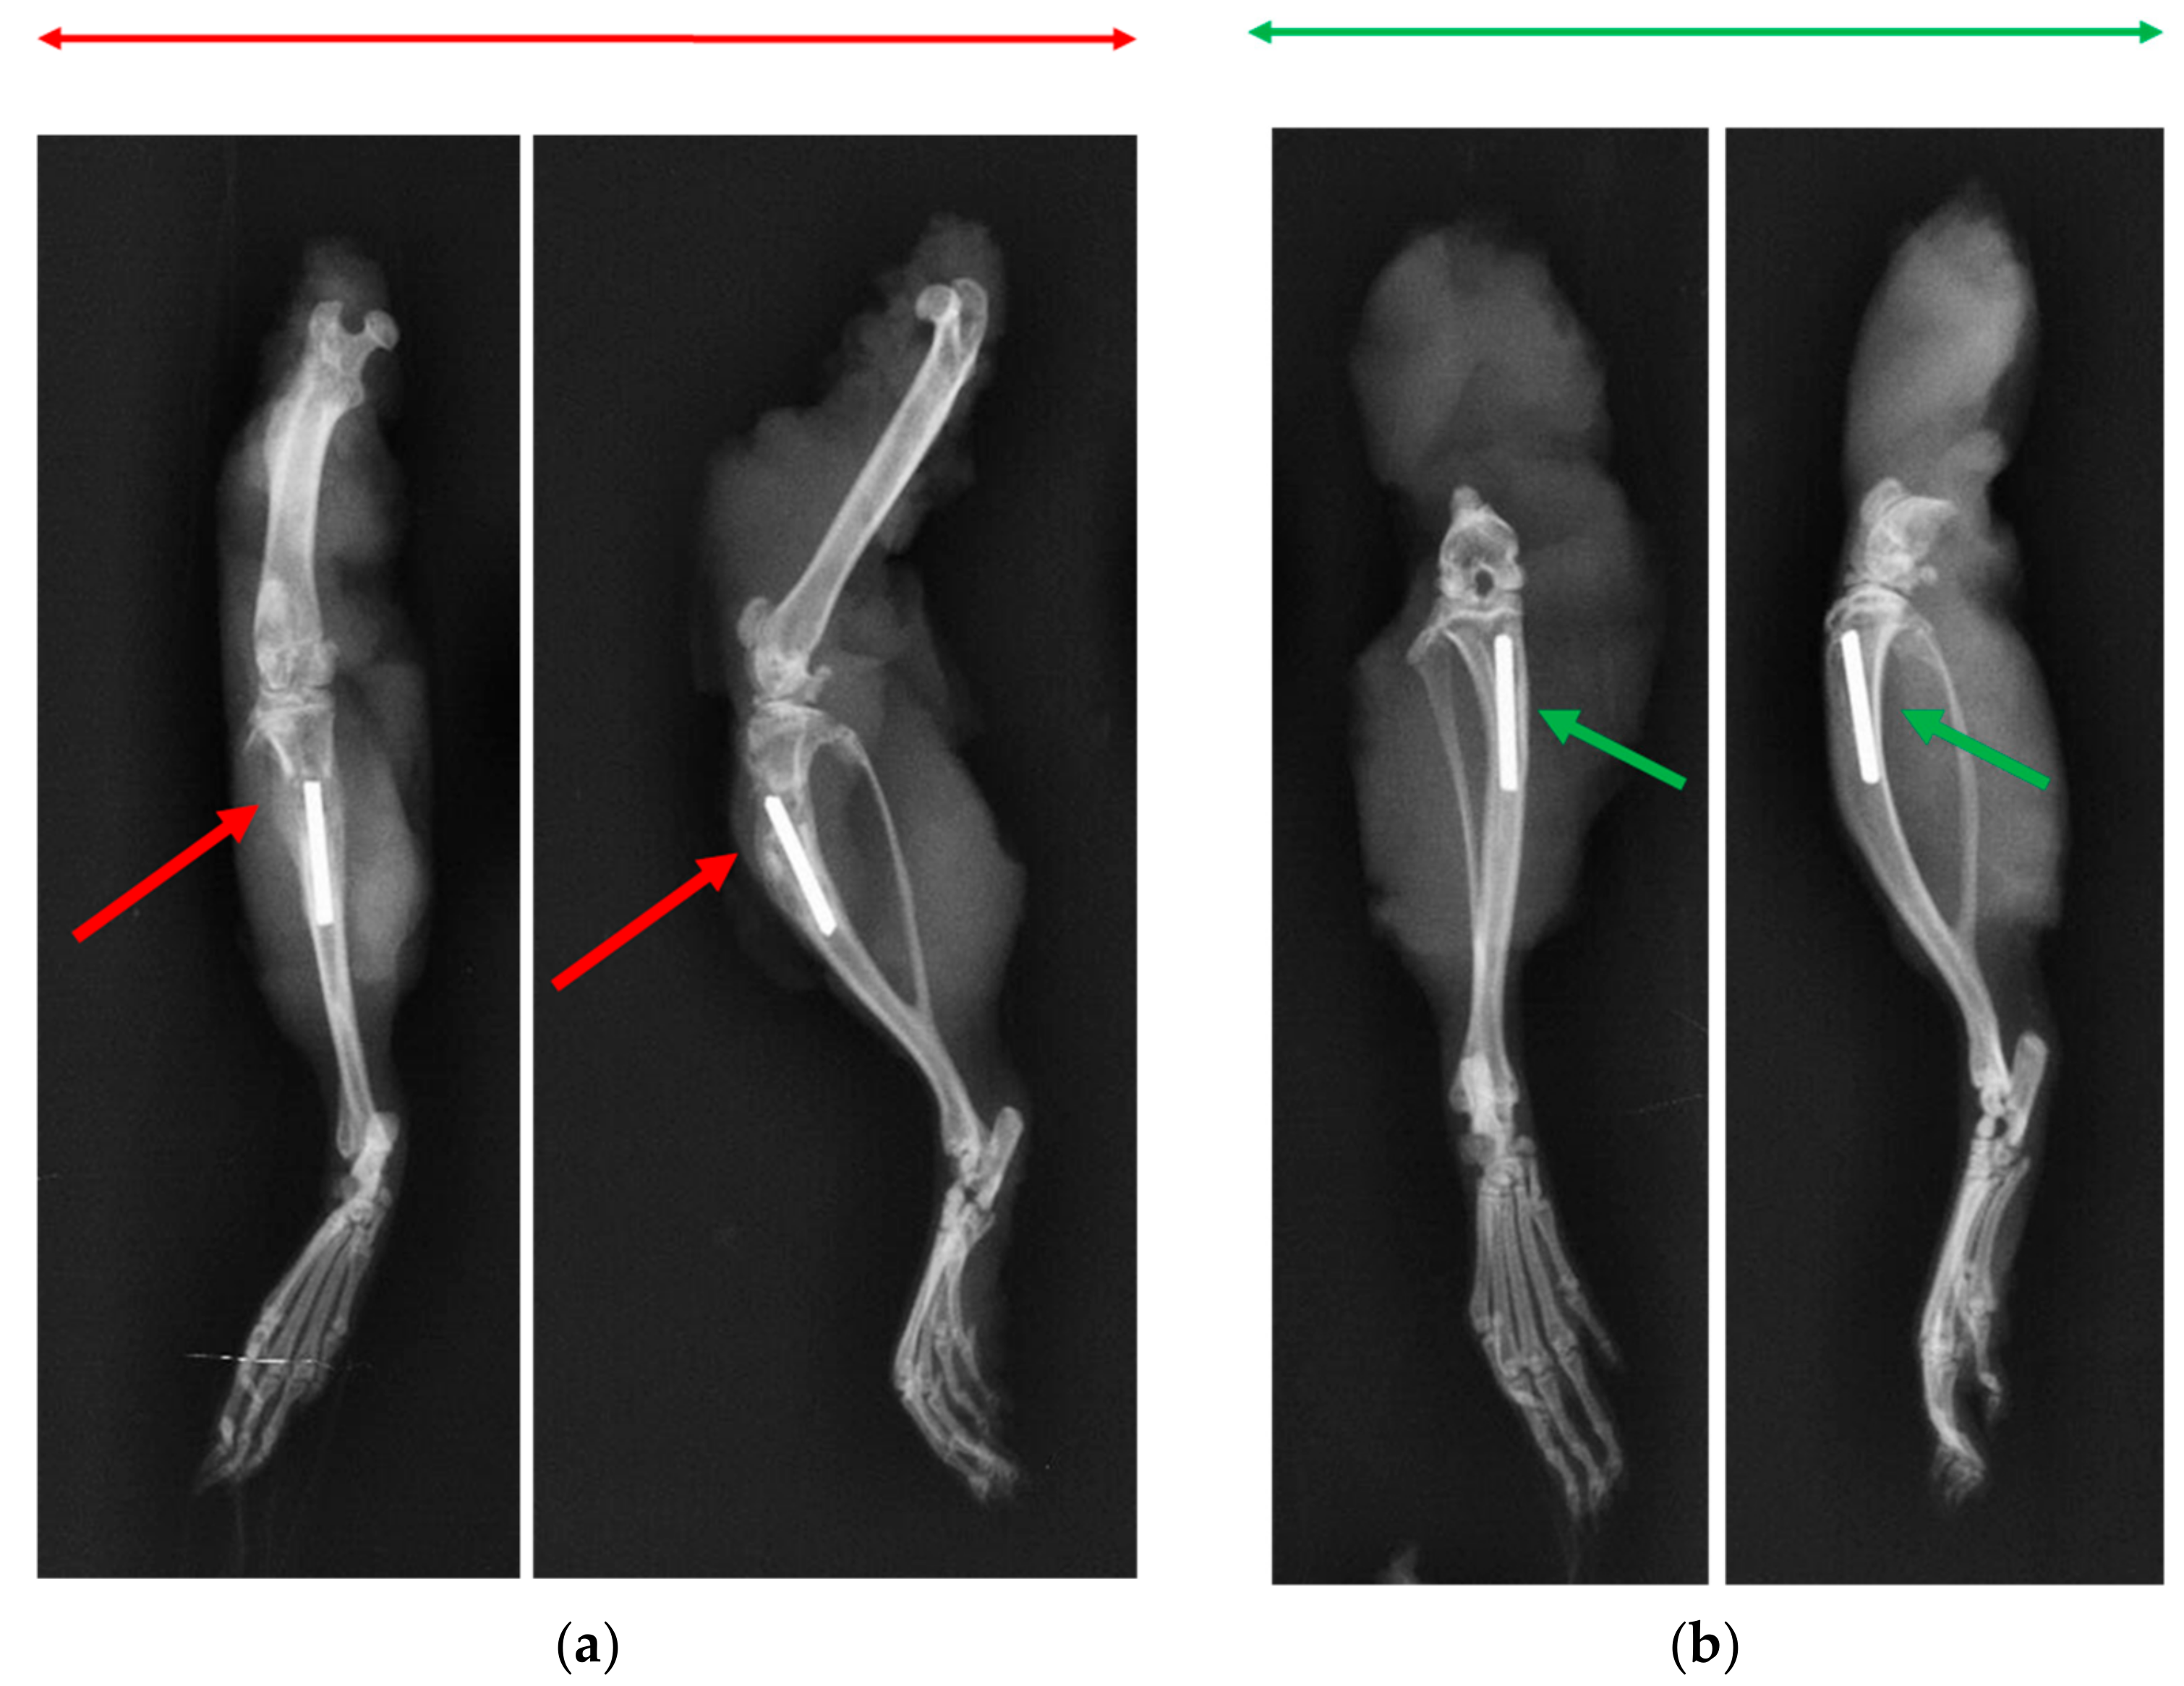

2.4.2. X-ray and Microcomputed Tomography (μ-CT)

3.6. X-ray and Microcomputed Tomography (μ-CT)

3.7. Bone Volume of Newly Formed Bone

4. Discussion